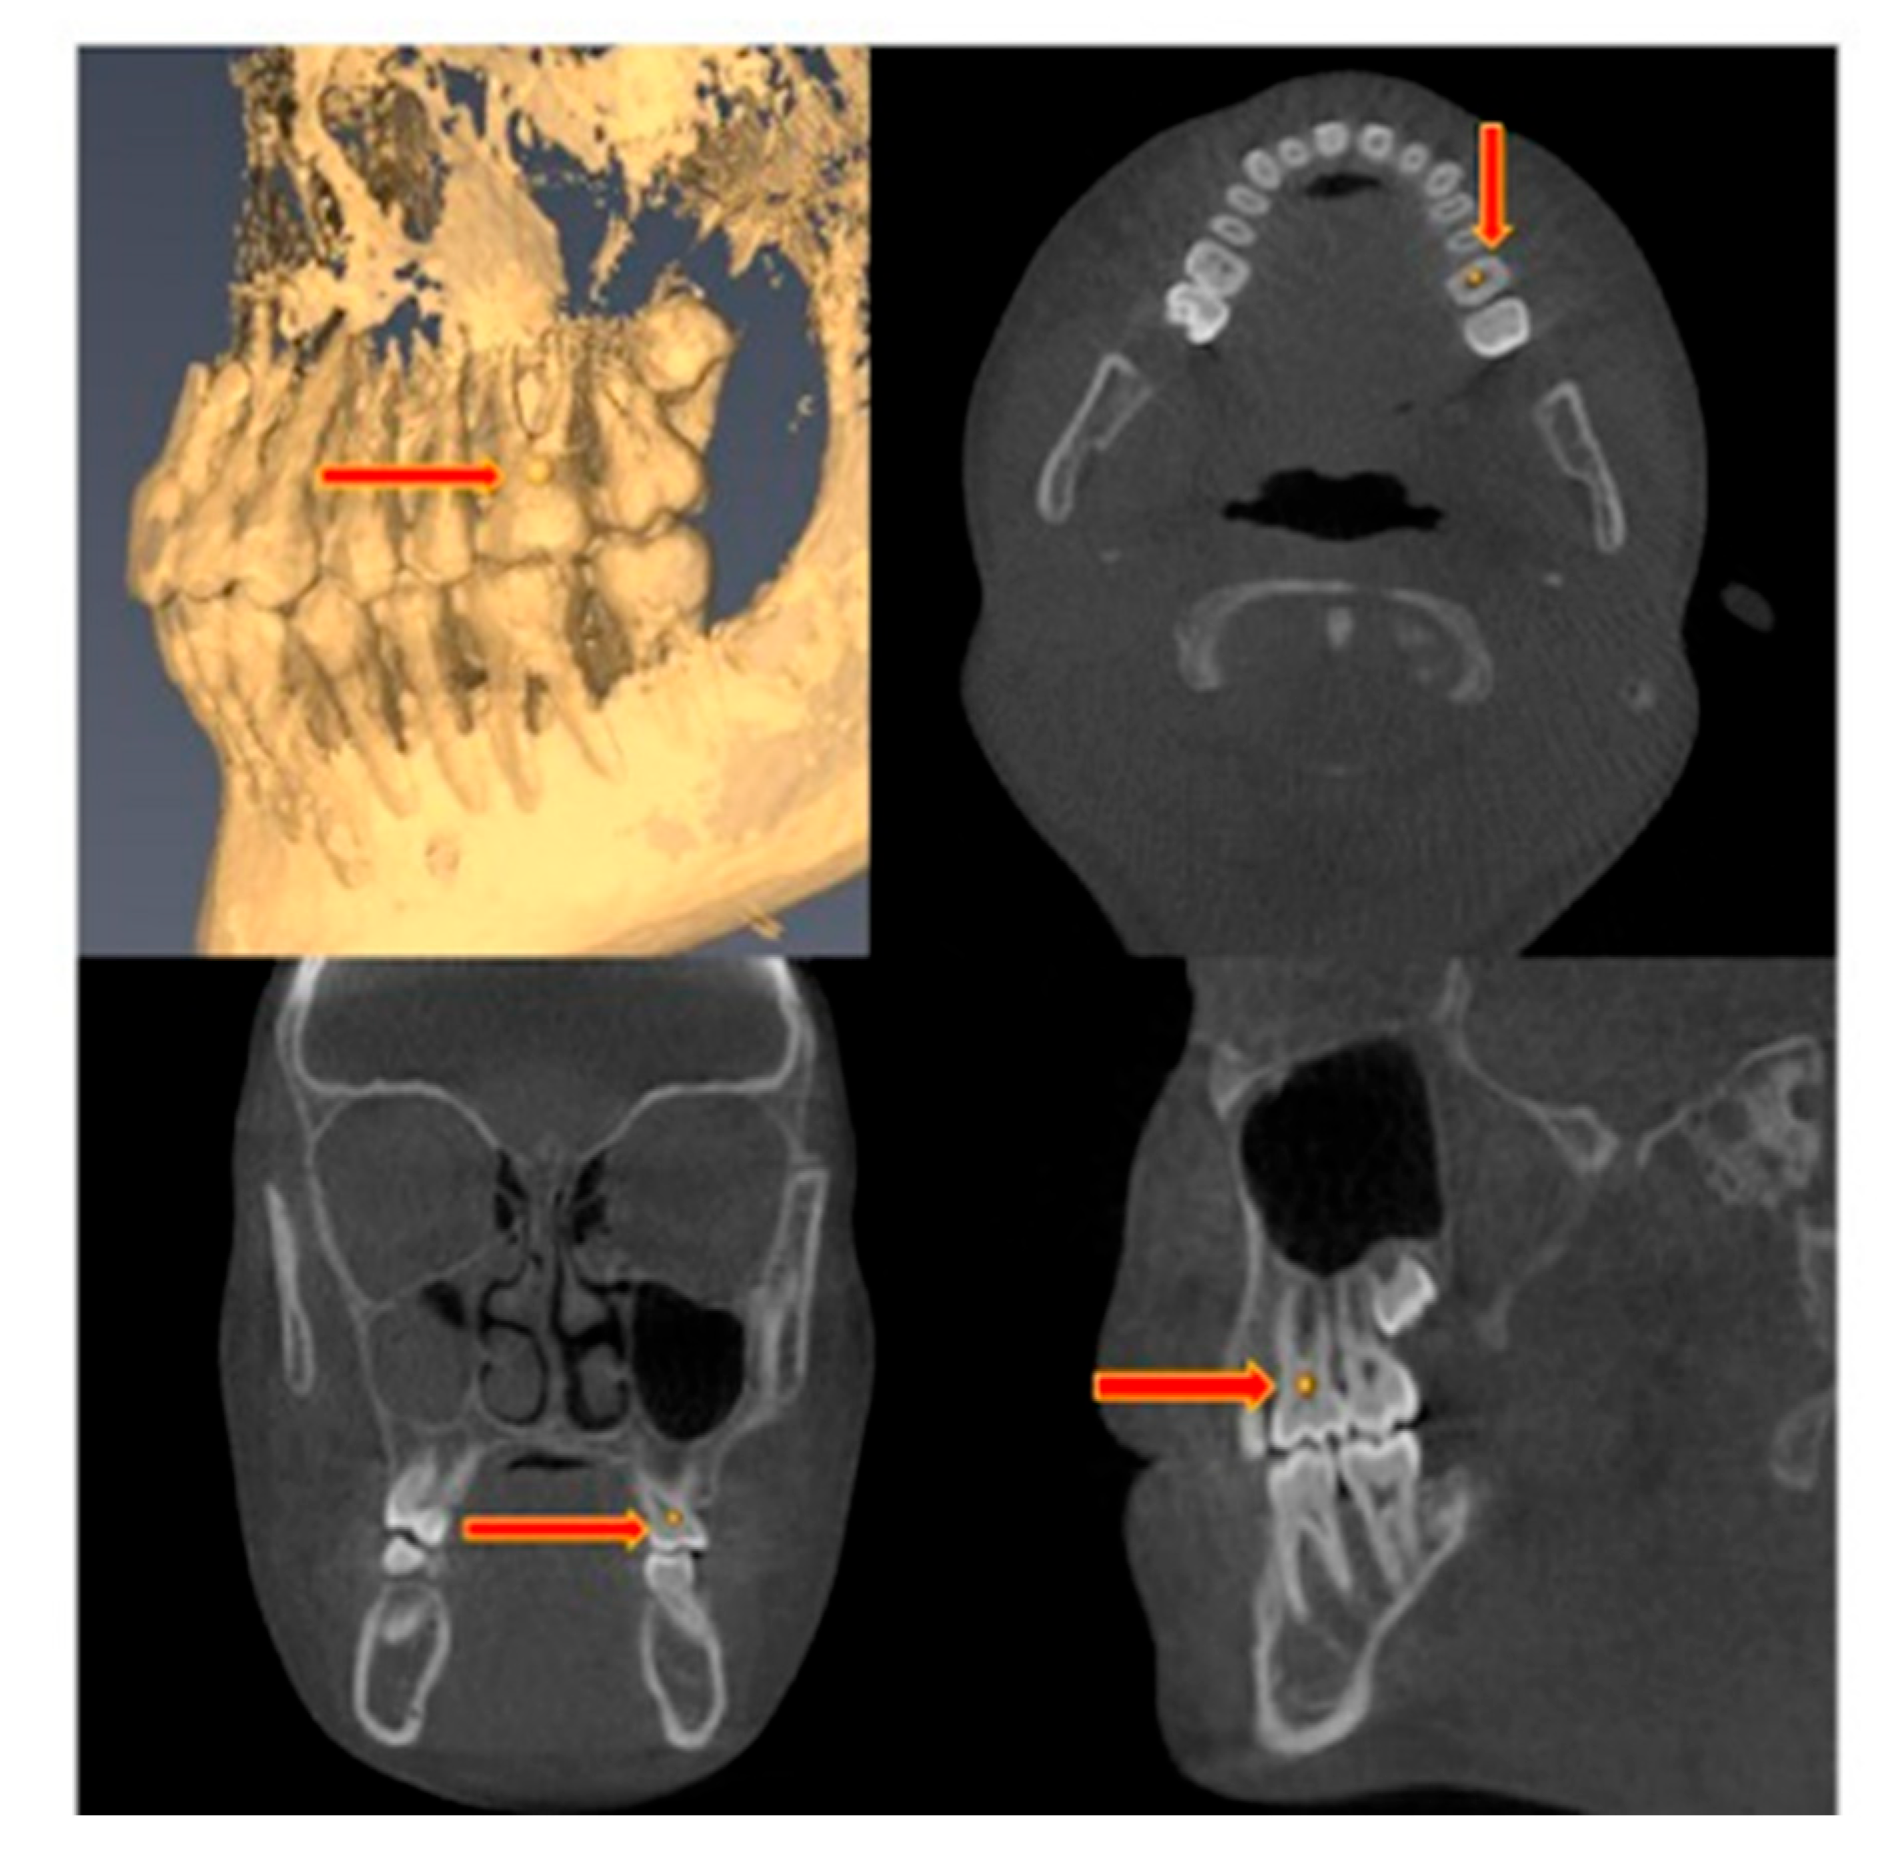

2.5. Measurement Method

2.5.1. Dental and Skeletal Distances

| Distance Measured | Definition |

|---|---|

| Dental | |

| Inter-molars (pulp chamber) | The distance measured between the pulp chambers of the right and left upper first molars |

| Inter-molars (root apex) | The distance measured between the mesiobuccal root apices of the right and left upper first molars |

| Inter-premolars (pulp chamber) | The distance measured between the pulp chambers of the right and left upper first premolars |

| Inter-premolars (root apex) | The distance measured between the buccal root apices of the right and left upper first premolars |

| Alveolar | |

| Inter-molars (alveolar bone) | The distance measured between the buccal cortices of the alveolar bone of the upper right and left first molars at the level of the mesiobuccal root apices |

| Inter-premolars (alveolar bone) | The distance measured between the buccal cortices of the alveolar bone of the upper right and left first premolars at the vertical level of the buccal root apices |

| Skeletal | |

| Inter-infraorbital | The distance measured between the right and left infraorbital foramina |

| Inter-greater palatine | The distance measured between the right and left greater-palatine foramina |